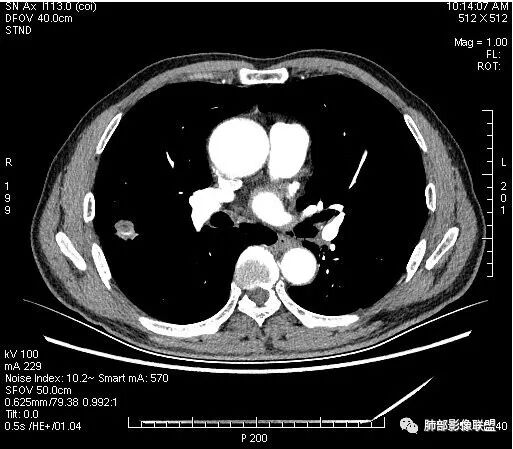

晨读:男,67岁,体检发现右肺结节。近圆形,支气管及伴行血管进入结节,进入结节后支气管堵塞,血管走形尚自然,结节内血管边缘凹凸不平。远端边缘见毛刺(软毛刺?)及分叶。见胸膜牵拉。实变中见空洞。整体膨胀感不明显。考虑炎性肉芽肿可能,隐球菌病可能性大。注意鉴别鳞癌、结核。

我说一下我考虑隐球的理由:

虽然良恶性征象都有,但是这个病灶增强后坏死比较明显,如果是恶性:腺癌这样大小的结节坏死很少见,只有低分化腺癌可以坏死,但是低分化腺癌这种大小一般会有周围转移表现(叶间胸膜结节,癌淋或者淋巴结明显肿大),如果是鳞癌,收缩力,坏死情况以及没有支气管截断都不太支持,而且结节远端有几个小结节样改变,大家可能认为是血管,但我觉得应该是卫星灶。所以觉得隐球可能较大。壁胸膜的牵拉线也没有引起胸膜凹陷,比较纤细,至于病理中的丝状物不一定是真菌菌丝。

这个病例确实有很多隐球菌的特点,包括周围的卫星灶、周围的毛刺,它没有粗短的毛刺,它是稍长一点、柔弱一点的。我是觉得这个符合脐凹征,所以我觉得恶性不能排除,结果错了,是炎性。

这个大部分边缘稍微偏平直一点,血管走行非常自然,包括里面的空泡征样的,影子很干净,边界很光滑,都是些炎性特点。

这么小的病灶同时有空洞和坏死,恶性不大好解释

这么小的结节,黄勇老师强调过,如果鳞癌,未经治疗,不会形成空洞,如果低分化腺癌可以坏死,但一般也不会有空洞,而且这么小的实性结节伴坏死的腺癌一般都会有转移

1.右肺上叶后段类圆形结节影,密度不均,有坏死空洞,坏死比较彻底,内外壁都较清楚。

2.病灶有浅切迹,没有深分叶,毛刺大多细长且柔软。

3.可见棘状突起及胸膜牵拉,但未见胸膜凹陷。

什么意思?结节影有牵拉的动作,但似乎“出工不出力”,收缩力羸弱!

4.病灶轻到中度强化。病灶内血管走行较完好,病灶旁血管局部显示粗大。

5.支气管关系不确定。

6.灶周见小结节影(卫星灶),边界不甚清晰。

会是肿瘤吗?

1.病灶整体太圆,没有深分叶,没有粗短毛刺,收缩明显乏力,强化不显著等等缺乏典型肺腺癌的影像学特征。腺癌如此小病灶出现空洞更是匪夷所思!

2.肺鳞癌易坏死,可病灶如此小即出现影像学上可见的彻底的坏死空洞也非常少见。

病灶内“旁若无人”的血管走形也让人难以理解。而该疑问也存在于结核病灶的辨析当中。

会是感染吗?

病灶相对局限,或偏安肺野一隅,小病灶带空洞,最常见的还是感染。

1.结核是常见的,坏死也够彻底,有卫星灶。疑问在于血管为什么不受累?

2.其他的慢性炎症。边界清楚符合慢性。慢性肺脓肿、隐球菌感染、奴卡菌感染等等都可以。可惜缺乏病原学依据。